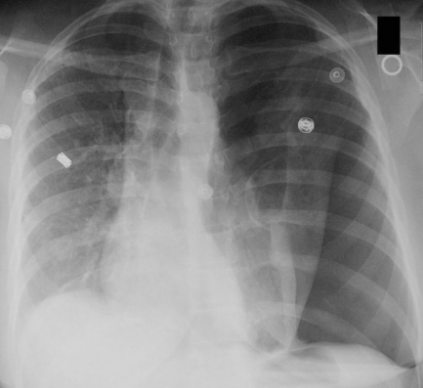

縦隔の中には血管や気管、食道があるがただのスペースであるので押されたりすると容易に動いてしまう。以下の胸部レントゲンでは左に気胸が起こり縦隔が右にシフトしている。他にも胸水、無気肺や肺線維症などでも縦隔のシフトは生じる。

Pneumothorax – Wikipedia, the free encyclopedia